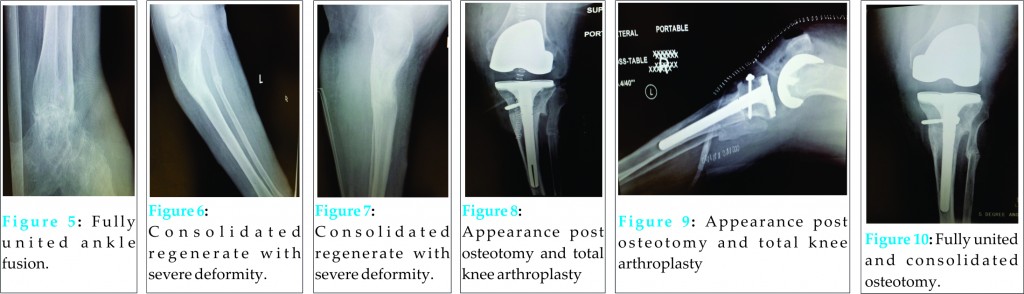

The patient failed to attend for regular follow-up, and represented at six months following index surgery complaining of worsening deformity. On examination, the proximal threaded rods of the circular fixator were bent and severe valgus deformity was apparent within both the frame and the limb. On questioning, it became apparent that the patient’s husband had been lengthening the medial aspect of the frame and compressing the lateral aspect. At this juncture, the regenerate, midfoot and hindfoot arthrodeses were deemed consolidated (figs 5-7), and the patient refused further frame treatment to correct the inadvertent proximal tibial deformity. Due to severely symptomatic pre-existing osteoarthritis of the knee, and a prior plan to perform total knee arthroplasty at a later juncture, a single stage intervention was proposed, utilising a stemmed total knee replacement and a simultaneous closing wedge osteotomy of the tibia to correct deformity and provide primary stability. At surgery, a standard medial parapatellar approach to the knee was performed, and the incision carried distally to the level of the metaphysis of the tibia. Due to severe intra-articular contracture, an extensile approach was performed via an osteotomy of the tibial tuberosity [5]. Standard femoral preparation was carried out. A separate lateral incision was used to perform a fibular osteotomy. An acute closing wedge osteotomy of the tibia was performed and the tibia realigned. Utilising intramedullary guidance, the tibia was prepared appropriately, and a tibial component with a canal filling stem used to bridge the osteotomy, correcting the deformity and simultaneously compressing the osteotomy (Figs 8 and 9). The tibial tuberosity was reattached with a large fragment screw. Uneventful osteotomy union subsequently occurred by three months post-operatively (Fig 10). Knee range of motion at final follow-up was 0-5-105 and no instability was reported by the patient.